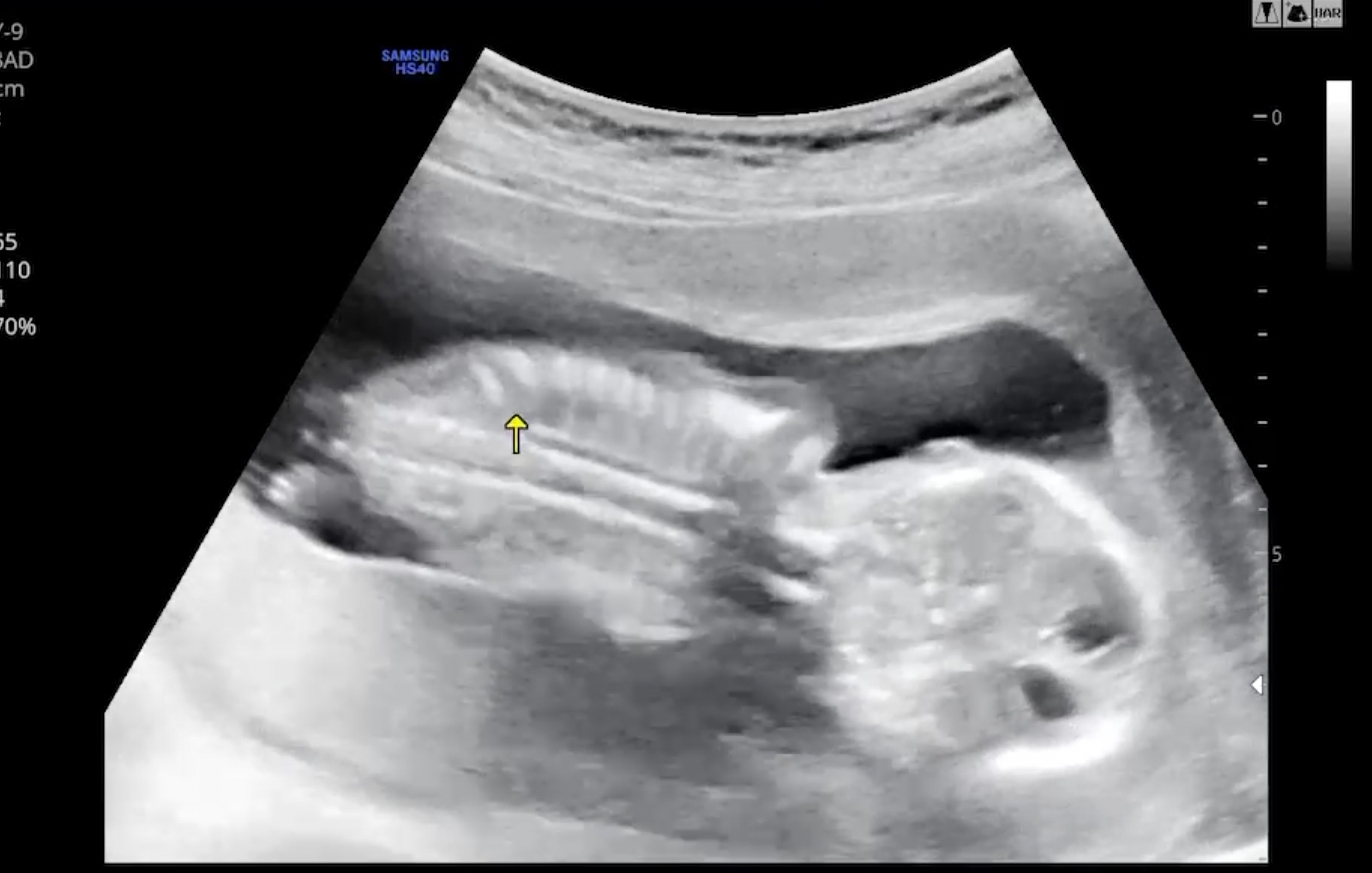

병원을 다녀온 이후에는 자궁확장공사를 잠시 쉬어가는건지 통증이 덜해졌어요. 뱃가죽이 늘어나는 느낌은 여전하지만요. 이번에 무무를 보러갔을 땐 자궁에 머리를 파묻고 엎드려 있었어요 ㅋㅋ

2주만에 더 자란 모습이더라구요. 11cm가 되었어요. 척추랑 갈비뼈까지 다 보여서 신비로움 반.. 당황스러움 반이었어요 ㅎㅎ

오늘도 눈이 뿅 마주쳤네요. 눈을 깜빡여줘서 더 신기했어요. 예전보다 더 볼에 살도 오른거 같아보여서 귀엽더라구요. 외계인에서 사람 형체로 점점 더 완벽해져가는중 ㅎㅎ~~